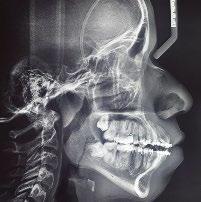

Se presenta un paciente de 18 años de edad que refiere tener hemofilia tipo A, moderado grado V. En los estudios de inicio extraorales, se observa en la Figura 1 el frente, sonrisa y perfil. En la radiografía lateral de inicio (Figura 2) se evidencian el overjet y overbite reducidos, clase I esquelética, hiperdivergencia y biprotrusión dentoalveolar.

Figura 2. Rx lateral de cráneo inicio.